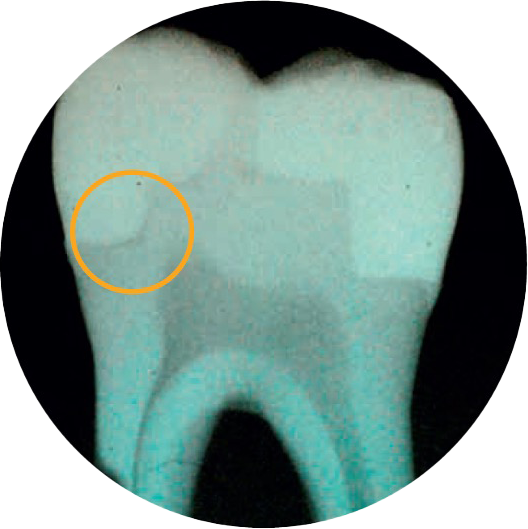

Sind haben Bedenken, dass sich Randspalten bilden?

2 von 3 Zahnärzten geben an, dass die Kavitätenadaptation das wichtigste Merkmal einer erfolgreichen Restauration ist.4

SDR flow+ ist ein Durchbruch in der Zahnmedizin – ein fließfähiges Bulk-Fill-Komposit mit selbstnivellierenden Eigenschaften und dem geringsten Schrumpfungsstress seiner Kategorie. Es ermöglicht eine Inkrementtiefe von bis zu 4 mm mit hervorragender Kavitätenadaptation und die Applikation randspaltfreier Restaurationen.